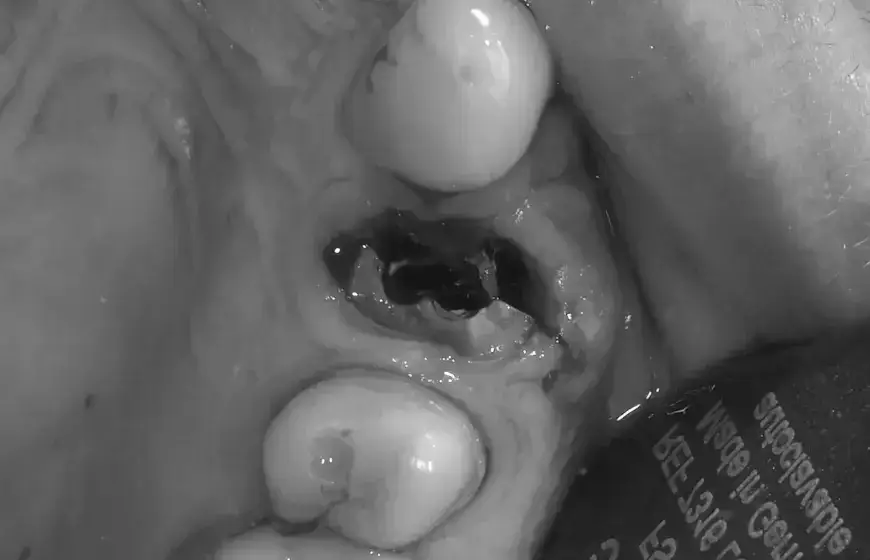

Suchy zębodół, znany również jako zapalenie zębodołu, to najczęstsze i najbardziej bolesne powikłanie po ekstrakcji zęba. Występuje, gdy skrzep krwi, który powinien chronić ranę, ulegnie rozpuszczeniu lub zostanie wypłukany, odsłaniając kość zębodołu. Odsłonięta kość jest niezwykle wrażliwa na bodźce zewnętrzne, co prowadzi do silnego, pulsującego bólu. Szacuje się, że suchy zębodół dotyka około 4% pacjentów po ekstrakcji, częściej występuje w żuchwie, zwłaszcza po usunięciu zębów mądrości (ósemek).

- Widoczny brak skrzepu w zębodole: Zamiast ciemnego skrzepu, w zębodole widać pustą przestrzeń lub szarawą, odsłoniętą kość.